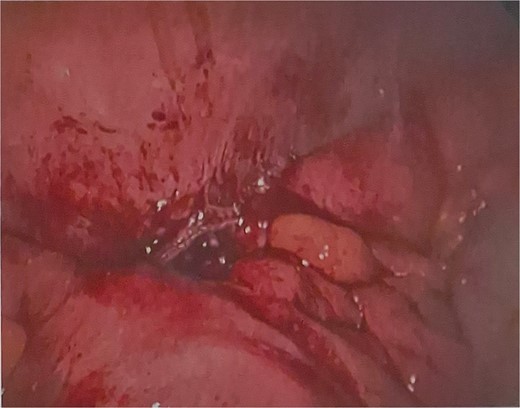

He was brought to theatre for a combined laparoscopic appendicectomy, drainage of peri-appendiceal abscess and cholecystectomy with intraoperative cholangiogram. Intraoperative findings included a 2 cm peri-appendiceal abscess cavity (Fig. 3) in keeping with pre-operative imaging. However, the gallbladder was gangrenous with a possible microperforation sealed by omentum (Fig. 4). Based on the intraoperative appearance, it was difficult to ascertain whether the abscess was due to primary appendicitis or whether the abscess was seeded from the cholecystitis and the appendix had become involved collaterally.

The cholecystectomy was performed first due to the evidence of gangrene. The gallbladder was decompressed, draining purulent bile, before dissection of the cystic duct and cystic artery to obtain the critical view of safety. Intraoperative cholangiogram was performed revealing a non-dilated biliary tree, clearly opacified upper ducts, no filling defects, and normal distal tapering with flow into duodenum. The gallbladder was dissected off the liver revealing a completely necrotic posterior wall.

Final histology showed gangrenous cholecystitis with evidence of perforation and a calculus lodged in the gallbladder neck. Appendix histology showed features in keeping with a perforated diverticula at the tip of the appendix with associated active inflammation and no fecalith, suggesting that the two pathologies occurred independently of each other.